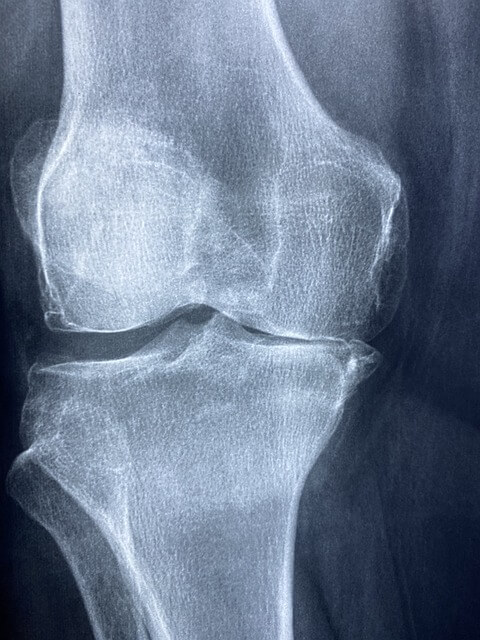

1. 관절 건강: MSM은 연골 형성 및 유지를 지원함으로써 관절 건강에 도움을 줍니다. 관절 통증과 염증을 완화하기 위해 그리고 쑤심과 붓기를 줄이기 위해 사용됩니다. 연구 결과 MSM이 동물 모델에서 관절염의 손상과 증상을 줄였다는 보고가 있습니다. 또한 인간의 경우 MSM을 복용하는 데 도움이 되는 것으로 나타났습니다.

5. 관절 통증: MSM은 관절 통증과 관련된 신경통증 및 염증을 완화하는데 효과적입니다. 관절 및 활동성을 개선하여 질병으로 인한 작업 부하와 통증을 줄이고 마디발증 치료에 유용하다고 알려져 있습니다.